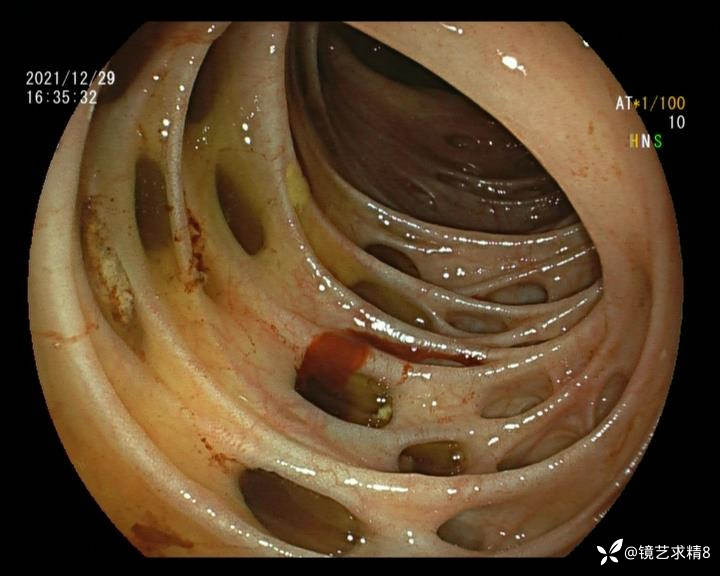

患者以消化道出血入院,胃镜未见异常,肠镜进入乙状结肠就看到很多憩室,同时还看到肠腔用清肠药后移动下来1枚尖锐的枣核,这么多憩室,这个枣核扎入憩室的机会非常大,推测应该是掉入一坑🕳就算出来还会有很多坑🕳🕳🕳等着,掉入憩室内很容易刺破血管,这可能就是消化道出血的原因,继续前进可以看到有一些憩室内翻,还有一些息肉,问题来了,那么多憩室,犯罪分子是抓住了,它在那些憩室内作过案?到达回盲部后挨个冲洗,但憩室大小又不足以把镜头进入憩室内观察,针对有血块的憩室冲洗后可疑出血的以夹子闭合或套扎,取出枣核,如果有锥形透明帽可能钻入憩室精准电凝效果更好,若内镜下操作失败介入治疗成功率更高,经内镜下治疗后观察未再出血出院。

目前研究认为,憩室出血与憩室内血管分布及走行有关。位于憩室颈部或基底部的局部动脉血管仅靠黏膜层与肠腔相隔,随着动脉本身退化或机械损伤,可破裂进入肠腔。值得注意的是,憩室出血通常与炎症无关,憩室炎很少发生明显的出血。

如何诊断憩室出血是临床面临的第一个难题,因为上消化道出血的发生率较高,常规便血患者需要排出上消化道出血的因素,进而进一步确认是否进行肠镜检查。憩室出血具有自发性停止的特点,往往骤起骤停,在出血间期或患者出现休克血压时结肠镜检查通常不能捕捉到近期憩室出血的表现。对于怀疑憩室出血的患者,往往需要更有耐心地反复冲洗观察,从而确认罪犯憩室。